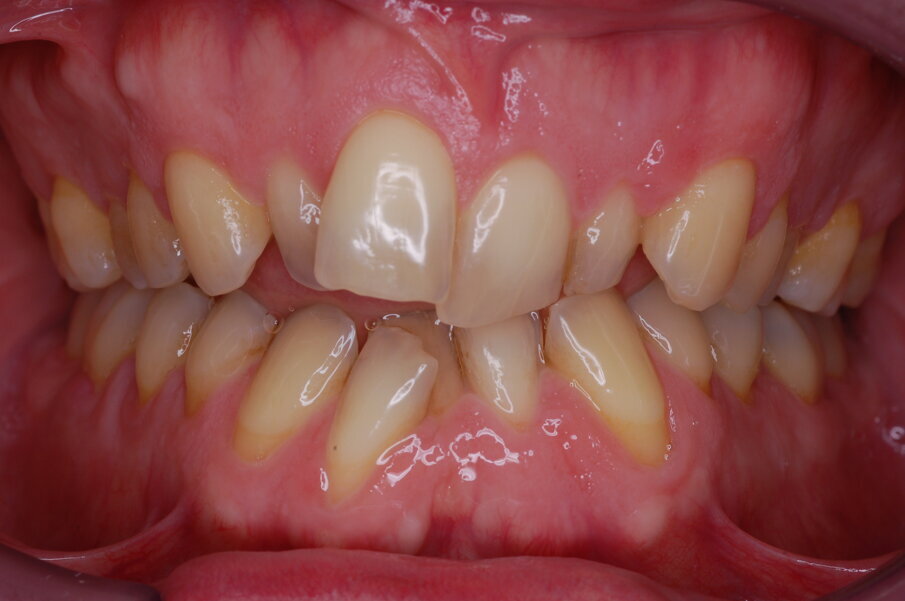

Diagnosi ed eziologia Un uomo sano di 39 anni si è presentato nel nostro studio ortodontico lamentando un aspetto dentale poco attraente e la paura della chirurgia ortognatica proposta da un altro ortodontista. Clinicamente, il profilo del paziente era rettilineo e la vista frontale non mostrava alcuna asimmetria facciale. L’esame funzionale non ha rivelato alcuna deviazione mandibolare o riduzione dei movimenti. Il paziente non aveva dolori articolari e non sono stati rilevati rumori articolari. Era presente una lieve occlusione molare bilaterale di Classe II, un morso aperto e un grave affollamento in entrambe le arcate. L’affollamento era particolarmente grave nell’arcata mandibolare, sebbene mancasse l’incisivo centrale mandibolare destro. Gli incisivi mascellari erano di piccole dimensioni, suggerendo una discrepanza dell’indice di Bolton se fossero stati presenti tutti e quattro gli incisivi mandibolari. Erano inoltre presenti un morso incrociato nella regione dell’incisivo laterale superiore sinistro e una grave rotazione distale del secondo premolare mandibolare sinistro (Figg. 1-8).

Figg. 1-8_Fotografie facciali e intraorali pre-trattamento.